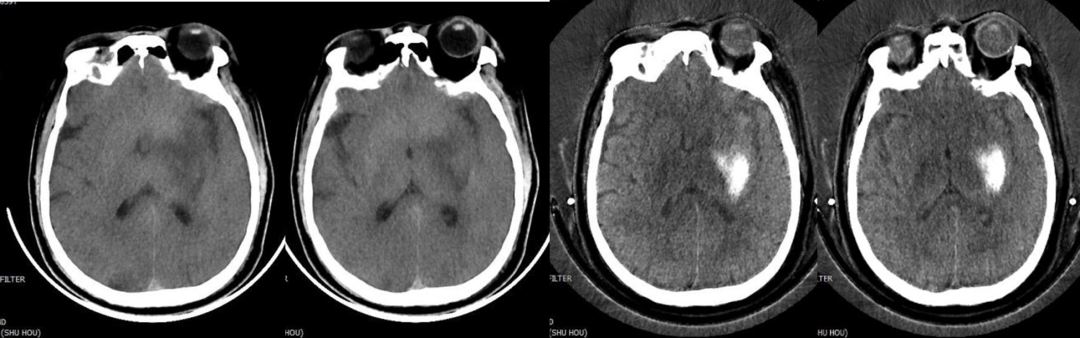

5.去金属伪影:能谱CT单能量成像结合MAR技术可在颅脑成像、颅内动脉瘤夹闭术后及骨关节金属植入术后复查中获得较好成像效果。